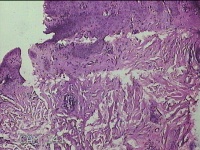

左手指结节

性别

男

年龄

42岁

临床诊断

皮下结节

一般病史

发现左手指结节2个月余。

标本名称

大体所见

灰白粉红色组织1x0.8x0.3cm一块,表面带梭形皮肤1x0.7cm,皮下见结节1x0.8cm,切开皮肤呈实性,切面灰白粉红色,质软。

图片无诊断价值。